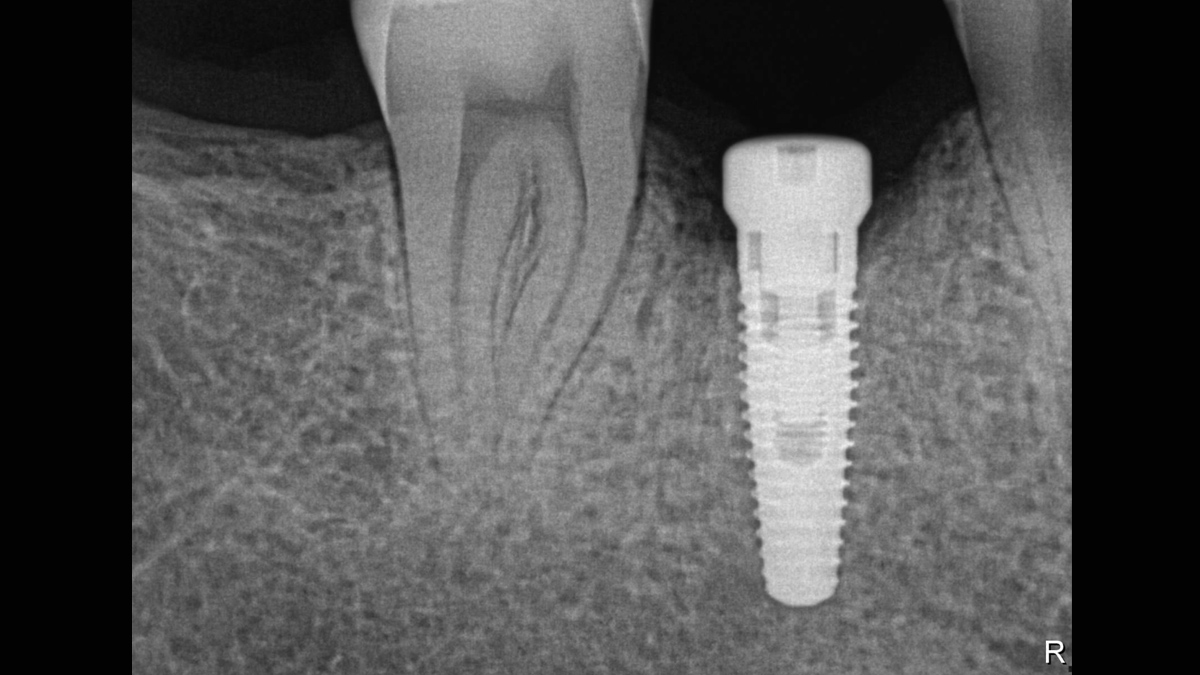

Working with Schick 33: Filtering enhancements

With Schick 33 sensors you have the option of five different filtering options: General Dentistry, Endodontics, Periodontics, Restorative and Hygiene. These clinically specific views are designed to optimize your diagnosis, enhancing the image to suit your needs.

Schick 33 - Gallery of Sample Images